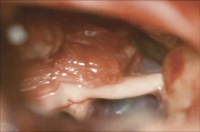

Thermokoagulation

Abbildung 4: Thermokoagulation: Punktionsstelle lateral des Mundwinkels in Richtung Foramen ovale rechts.

Keywords: FotoNeurochirurgieThermokoagulation